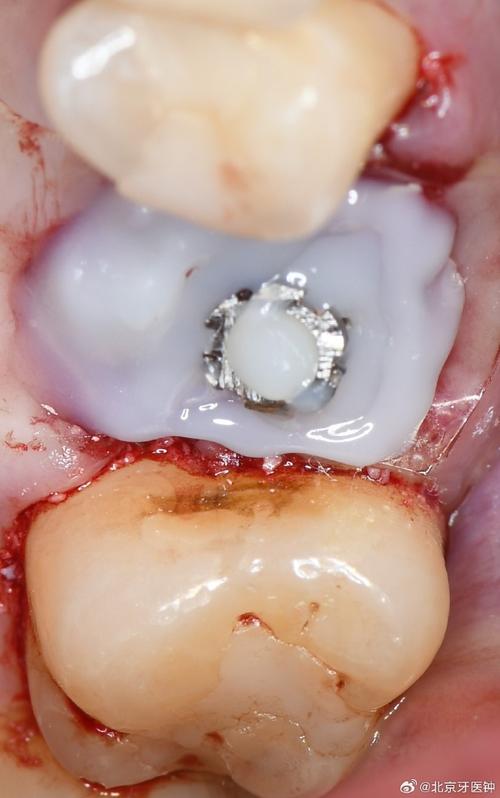

戴牙冠后1-2周:功能适应期

当骨结合完成后,医生会在种植体上安装牙冠,恢复牙齿外形和功能,此时需适应新的“牙齿”。

- 咬合调整:初戴牙冠时,可能出现咬合过高、酸痛或异物感,医生会通过调磨牙冠确保咬合平衡,避免早接触(某一点先受力)导致创伤。